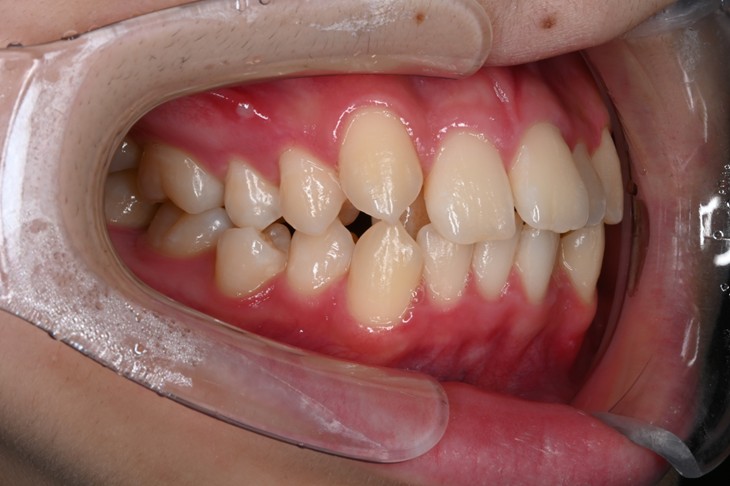

症例2:八重歯が気になる

| 患者様データ | 20代 女性 |

| 来院主訴 | 八重歯が気になる。 |

| 治療内容 | 八重歯を治すために上の親知らずを抜歯し、インビザラインにてマウスピース矯正を開始しました。かみ合わせを整えるためにゴムかけを行いました。 |

| 概算治療費 | 約85万円 |

| 治療期間 | 1年3ヶ月 |

| 通院回数 | 8回 |